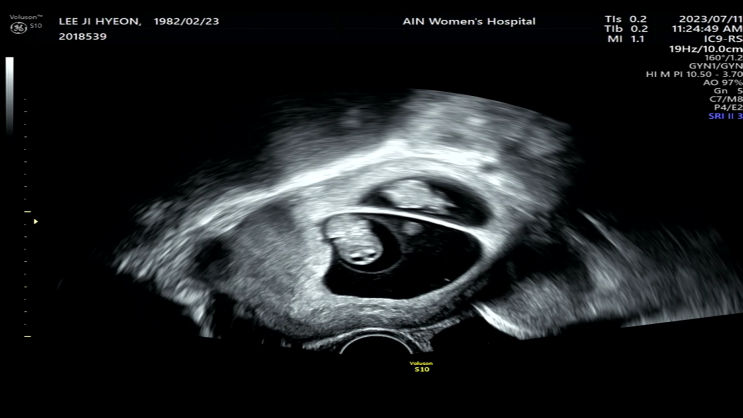

[임신일기]7주 4일차 / 얼마나 잘 자랐을까?

1주만에 간 난임센터 시험관 한 산모들은 한주 사이에 아이들이 잘못됐을까봐 걱정한다던데, 난 기립성 저...